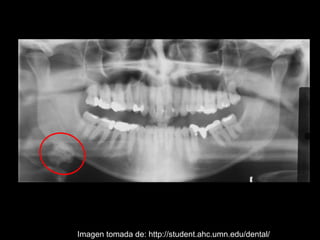

La sialolitiasis es la formación de obstrucciones mineralizadas en las glándulas salivales, causadas por el depósito de calcio y fósforo. Puede presentarse en las glándulas salivales mayores y menores, causando inflamación e hinchazón e incluso dolor durante las comidas. Los sialolitos se ven en radiografías como densidades radiopacas de varias formas y tamaños dentro de los conductos glandulares. El diagnóstico diferencial incluye otras imágenes radiopacas en los tejidos blandos.